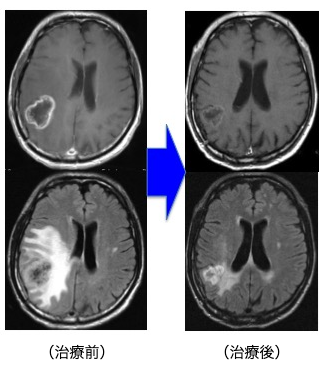

前述の如く、神経膠腫(グリオーマ)は、一部の腫瘍を除き手術のみで完治させることはできません。従って、術後に放射線治療と化学療法は不可欠です。手術後にどのような補助療法を行なうかは施設により意見が分かれるところです。しかし最近では欧米を中心に、複数の施設による大規模で多数の患者に対して信頼性の高い試験が行われております。我々はそれらの最新結果を基にして十分な説明を行い、納得・同意を得た上で補助療法を決定しております。放射線治療を主軸に化学療法を併用する標準治療が原則ですが、特に化学療法剤であるテモゾロマイド (TMZ)は経口投与の可能な薬剤であり、副作用が少なく簡便に治療ができます。当科でも従来の化学療法を凌駕する治療成績の向上がみられています。

Grade 4(膠芽腫):手術+放射線治療+化学療法(TMZ±Bev(アバスチン))±交流電場腫瘍治療(NovoTTF)

放射線治療に化学療法を併用します。(治療期間は6週間ですが、高齢者の場合は放射線治療を3週間に短縮して行うこともあります。その場合でもTMZは6週間使用します。)